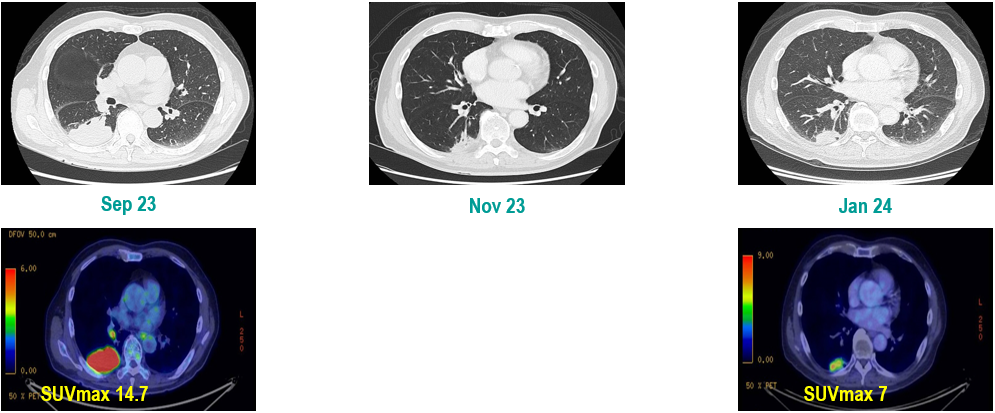

PET-CT(2023年9月):右下肺叶发现6.9×6.7×6.6cm的FDG高摄取肿块,伴右侧第7、8肋骨侵犯可疑,右肺门淋巴结肿大,双肺上叶多发结节,考虑腺癌谱系疾病。

CT及PET-CT随访(2023年11月、2024年1月):评估新辅助治疗效果,右下肺叶肿块缩小,右肺门淋巴结代谢活性消失,右肺上叶结节稳定但代谢活性降低,左肺上叶及双侧磨玻璃样病变稳定。

新辅助治疗:患者接受4周期新辅助化疗联合免疫治疗(培美曲塞、顺铂、纳武利尤单抗),治疗后影像学显示肿块缩小,代谢活性降低。

手术治疗:2024年1月行右肺下叶切除术及右肺上叶楔形切除术,术中病理显示右肺下叶为腺癌伴SCLC灶,右肺上叶为腺癌。术后病理分期:右肺下叶腺癌为ypT2aN0M0(IB期),伴SCLC灶,考虑为治疗后转化;右肺上叶腺癌为ypT1bN0M0(IA2期)。